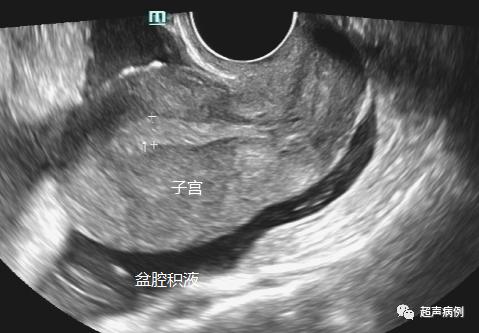

下图就是分别经腹部及经阴道超声的检查对比图。

可以看出经腹部的超声不能看清较小的卵泡及卵巢的细微结构,而经阴道超声就能看得清清楚楚。